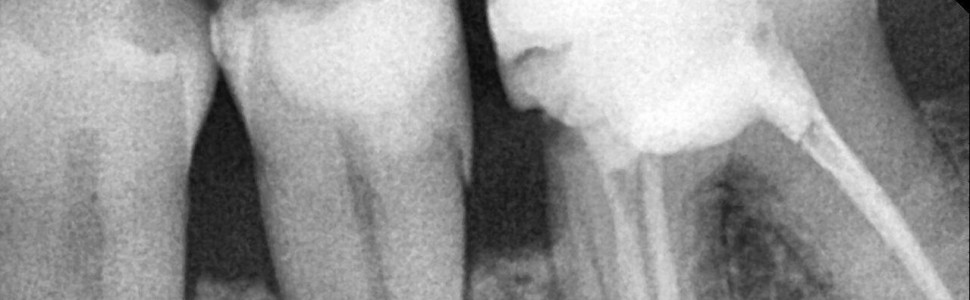

Zgłosił się do mnie pacjent, którego skierowano do specjalisty periodontologa w celu konsultacji i leczenia ubytków kostnych w okolicy zębów 34-36. Pacjent jest ogólnie zdrowy. W trakcie wywiadu ogólnostomatologicznego zgłaszał dyskomfort oraz krwawienie dziąseł podczas szczotkowania zębów, utrzymujące się od wielu miesięcy. Na zdjęciu RTG celowanym dostarczonym przez pacjenta stwierdziłam ubytki nadkostne w okolicy 34-36. Jakie działania powinnam podjąć?

W opisanym przypadku stwierdzono: złogi naddziąsłowe i poddziąsłowe, uogólniony obrzęk i zaczerwienienie dziąseł, krwawienie – BOP >70%. Głębokość sondowania oceniono w 6 punktach przy wszystkich zębach. Otrzymane wartości oscylowały w granicach 5-8 mm, w okolicy zęba 35 na powierzchni dalszej wartość PD wynosiła 9 mm.

W przypadku, gdy pacjent osiągnął prawidłową higienę jamy ustnej (FMPS<20%), ale utrzymuje się stan zapalny (BOP+), a PD ≥5,5 mm, można rozważyć leczenie chirurgiczne. Obecność ubytku nadkostnego skłania do wyboru minimalnie inwazyjnego zabiegu oczyszczenia po podniesieniu płata (open flap debridement – OFD). Zabieg taki pozwala na eliminację zapalenia i spłycenie kieszonek patologicznych, ale może też generować recesję dziąsła. Dlatego wykonanie OFD w odcinku przednim jest przeciwwskazane. Widoczne na RTG nadkostne ubytki w okolicy 34-36 nie dają możliwości odtworzenia tkanek przyzębia, a więc są przeciwwskazaniem do periodontologicznych zabiegów regeneracyjnych.

Ryc. 1. Nadkostne ubytki w okolicy 34-36.